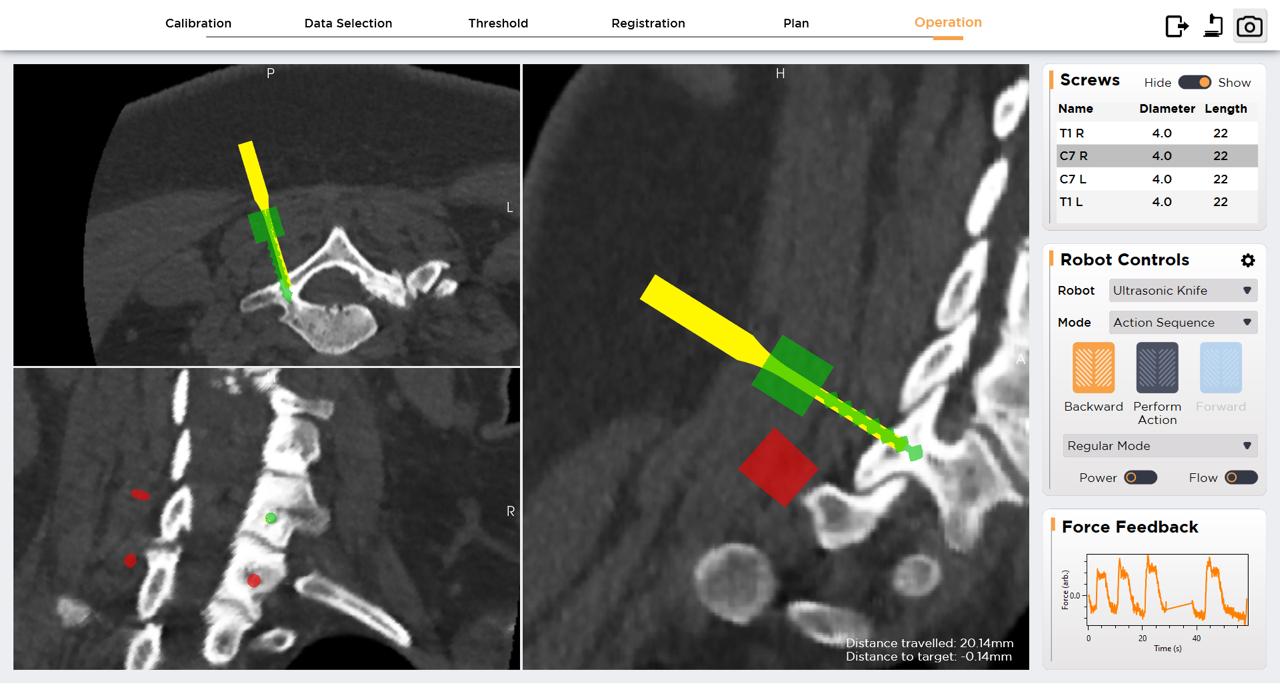

Personalized locomotor training with non-invasive spinal cord stimulation for functional recovery after spinal cord injury

Umema Rafay

Muhammet Kocer

Attiyeh Vasaghi

Katrina Armstrong

Sydney Sass

Kristine Cowley

Katinka Stecina

Screenshot 2025 06 01 at 4.31.20 pm

Screenshot 2025 05 28 at 10.55.33 pm

• Over 80,000 Canadians live with spinal cord injury (SCI), which can lead to complete or partial loss of motor, sensory and autonomic function.